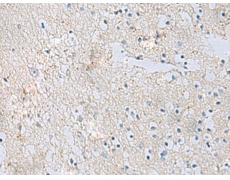

IHC positive control: |

Human brain |

IHC Recommend dilution: |

50-100 |